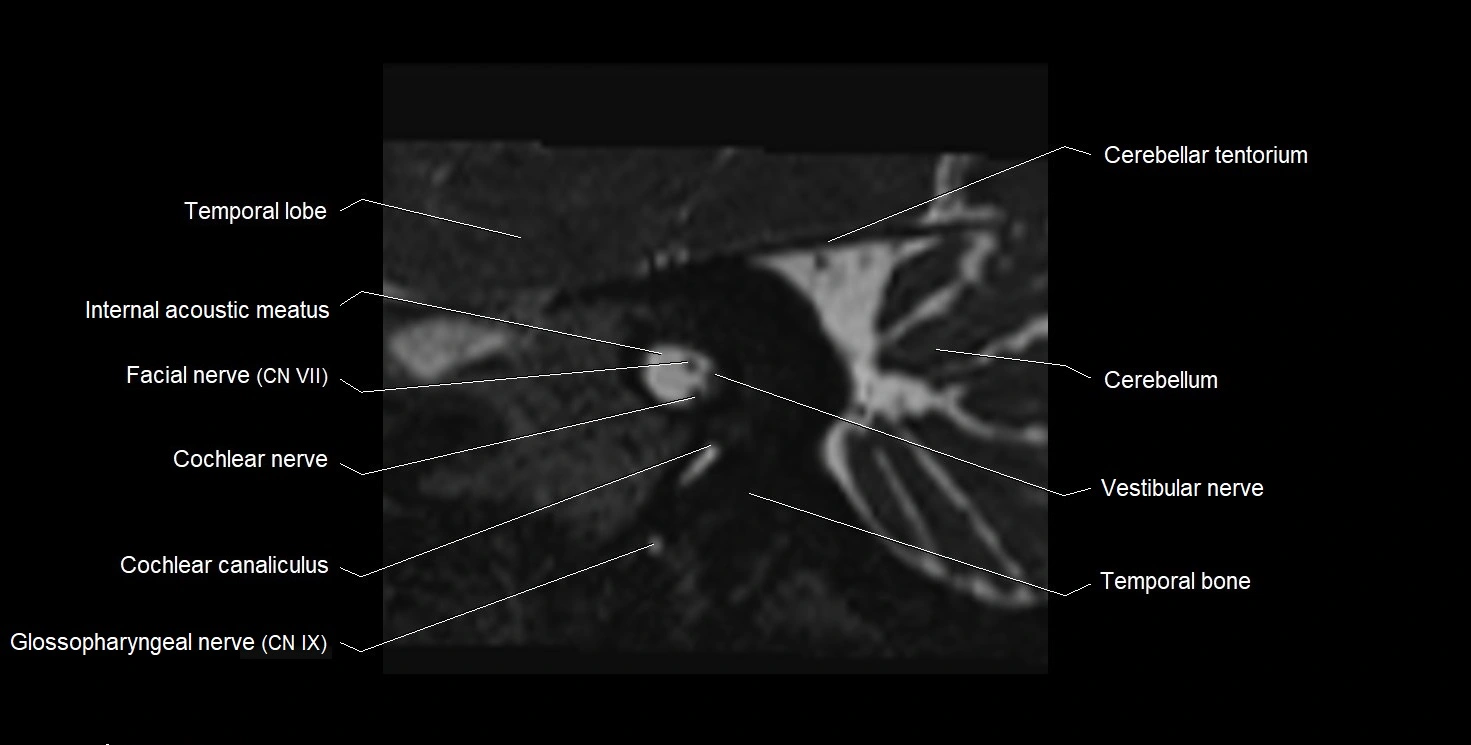

MRI Appearance

• The abducens nerve is a small, thin, linear structure

• Best visualized on high-resolution T2-weighted 3D MRI sequences (e.g., FIESTA or CISS)

• Seen as a hypointense (dark) line running from the brainstem at the pontomedullary junction, traversing the prepontine cistern, and entering Dorello’s canal under the petrosphenoidal ligament, then into the cavernous sinus, and finally the orbit

• May be challenging to visualize in standard MRI due to its small size

• Pathology may be inferred by absence, displacement, or enhancement of the nerve

MRI images

image